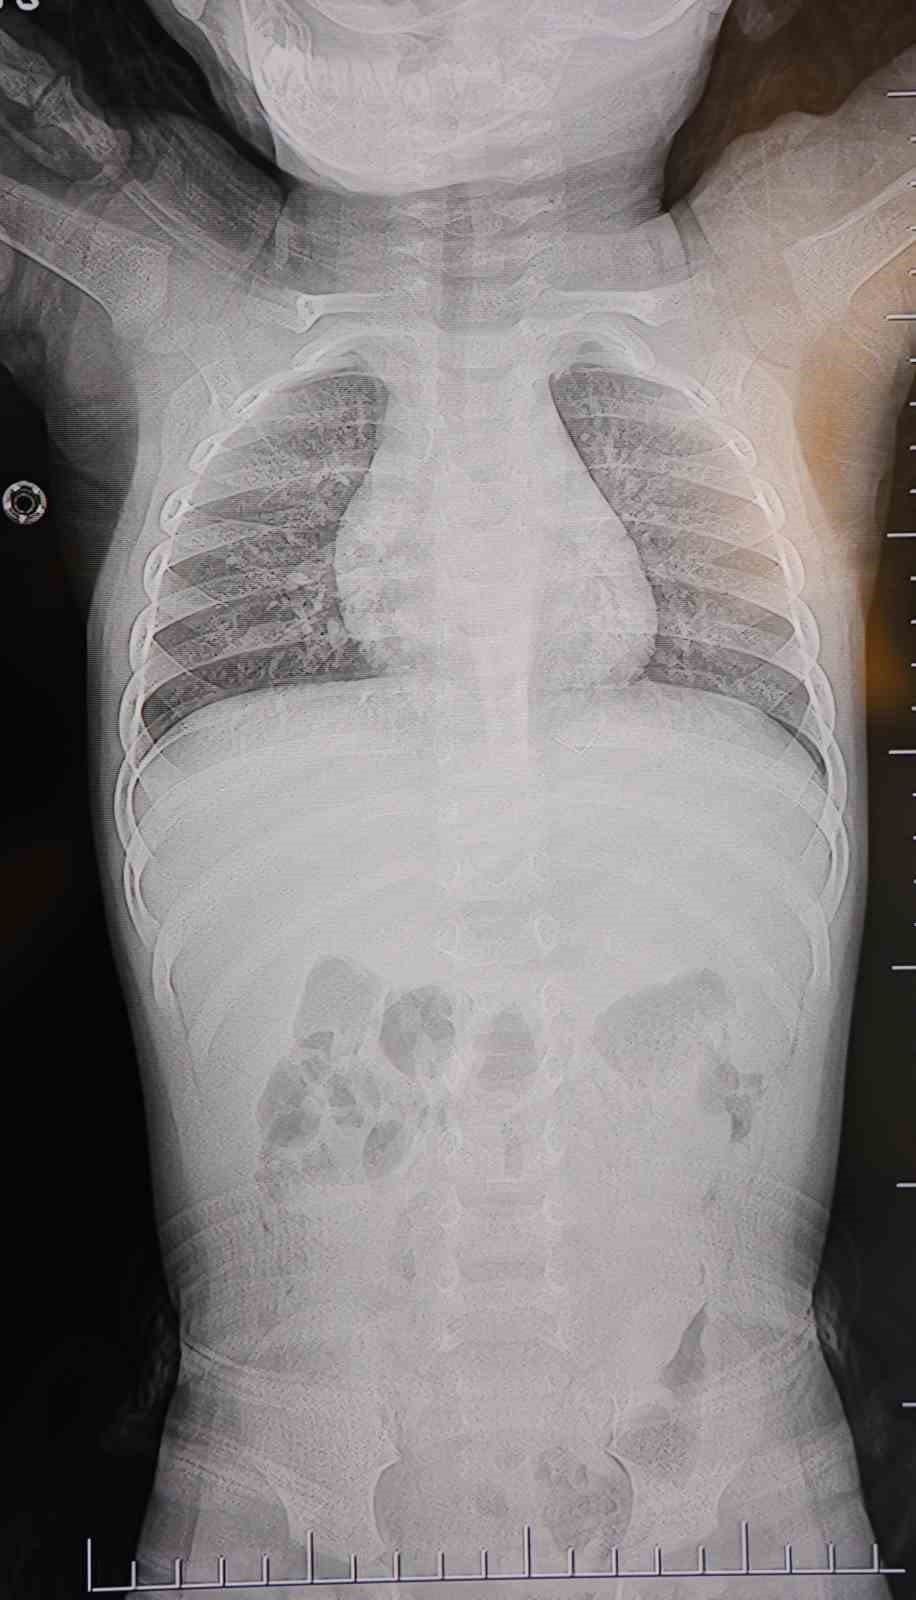

Alınan bilgiye göre, Kahramanmaraş’ta farklı ortopedi, çocuk cerrahisi ve beyin cerrahisi kliniklerine başvurusu yapılan bir yaşındaki bebeğin, sırt bölgesinde yabancı bir cisim olduğu ancak müdahalenin zor olduğu ve 8 yaşına kadar beklenmesi gerektiği bildirildi. Aile, bebekleri için son olarak HG Hospital’e başvurdu. HG Hospital Beyin ve Sinir Cerrahisi Uzmanı Prof. Dr. İdris Altun tarafından yapılan tetkiklerde, yabancı cismin cilt altında, omurilik kanalına yakın bir bölgede olduğu ve akciğer zarına doğru ilerlediği belirlendi. Hasta, genel anesteziye alınmadan, lokal anestezi ve sedasyon eşliğinde ameliyata alındı. Yapılan müdahalede yabancı cisim tamamen çıkarıldı. Çıkarılan cismin, ince zımba teline benzer metal bir tel olduğu ve yaklaşık 2 santimetre uzunluğunda bulunduğu tespit edildi. Hasta, aynı gün taburcu edildi.

Konuya ilişkin açıklama yapan Prof. Dr. İdris Altun, “Sırtında yabancı bir cisim olduğu söylenmiş ancak çıkarılamayacağı ve 8 yaşına kadar beklenmesi gerektiği ifade edilmişti. Bize başvurduğunda yaptığımız tetkiklerde, cilt altında, omurilik kanalına çok yakın ve akciğer zarına doğru ilerleyen bir yabancı cisim tespit ettik. Hastamızı tamamen uyutmadan, lokal anestezi ve sedasyon eşliğinde müdahale ederek lezyonu tamamen çıkardık. Çıkardığımız cismin ince zımba teline benzer, yaklaşık 2 santimetre uzunluğunda metal bir tel olduğunu gördük. Bu yabancı cisim alınmasaydı, bölgede enfeksiyon gelişebilirdi. Enfeksiyon sonucu omurilik kanalında ciddi hasarlar oluşabilir, çocuk büyüdükçe cismin hareket etmesine bağlı olarak omurilikte zedelenmeler meydana gelebilirdi. Ayrıca yana doğru ilerleyerek akciğer zarına ve akciğere batma riski vardı. Bu da enfeksiyona ve ilerleyen süreçte tümörle karışabilecek tablolara neden olabilirdi. Şu an hastamız gayet sağlıklı. Gerekli kontrolleri yaptık ve aynı gün taburcu ettik” dedi.